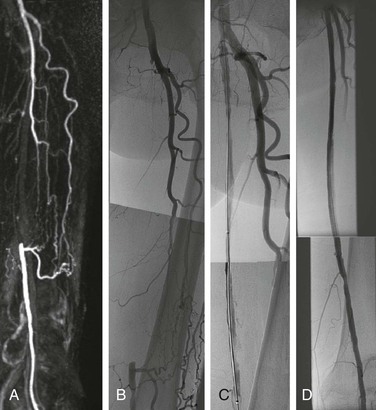

Occlusion of a major lower extremity artery is a primary stimulus to the enlargement of pre-existing collateral vessels, and the superficial femoral artery (SFA) is the most common site of lower extremity arterial occlusions (4).